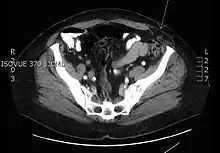

Transverse CT image of the abdomen in a patient with a Spigelian hernia (arrow). | |